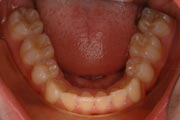

Crowding

Before